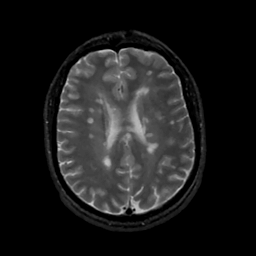

MR Study #15, June 9, 1991 -- Slice #32